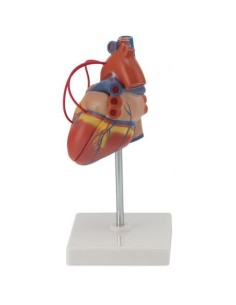

Du crâne en 22 parties à verrouillage magnétique aux modèles de colonne vertébrale, des modèles d'articulation aux modèles de cœur, chaque pièce de notre collection est conçue pour une immersion totale dans l'étude de l'anatomie humaine. Nos modèles, réalisés à partir de scans d'os réels, garantissent une expérience tactile authentique et une fidélité de poids presque identique aux originaux.

Indispensables aux étudiants comme aux professionnels, nos modèles anatomiques sont des outils pédagogiques qui permettent d'observer les structures anatomiques avec précision, en évitant les dissections ou les études invasives. Ils sont également utiles pour expliquer les pathologies aux patients, ce qui rend la communication plus efficace et permet de gagner un temps précieux.